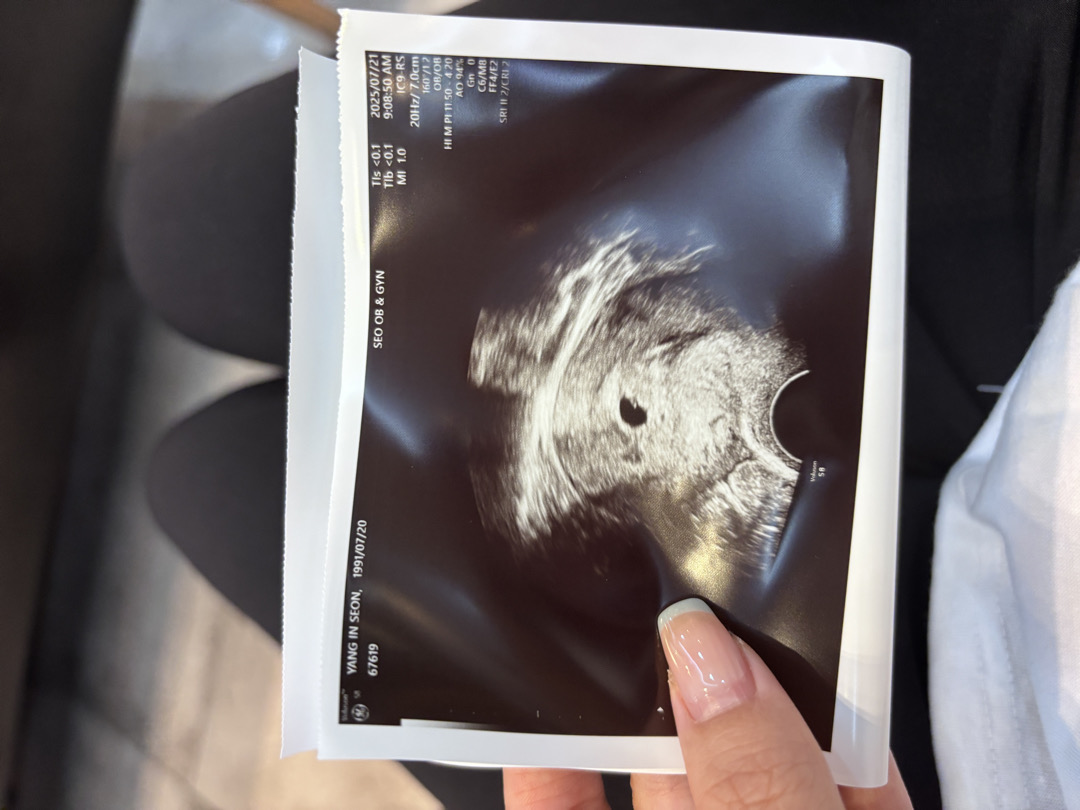

오늘 아기집 보고 왔어요!

6/17 막생이고 날짜가 애매해서 초음파로 보일지 걱정이였는데 다행히 오늘 병원진료 받았는데 아기집보이더라구요 2주뒤에 내원하면 심장소리 들을 수 있다는데 시간이 빨리 갔으면 조켓어요🙏